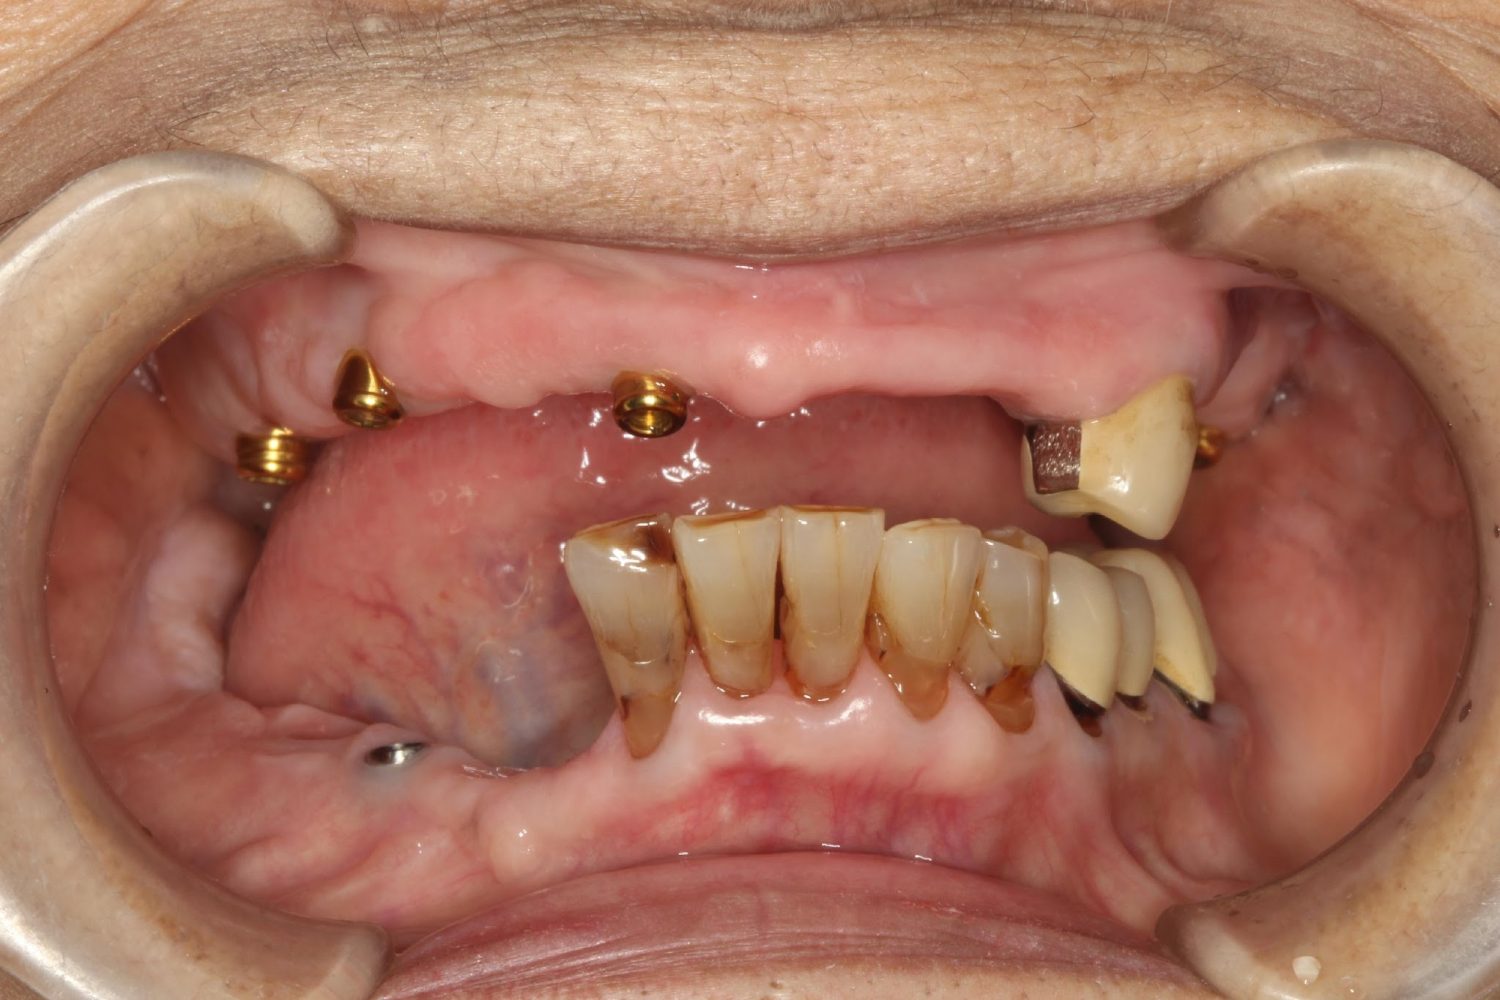

多数歯う蝕および多数歯欠損による咬合崩壊、保存不可能な歯の抜歯により上下無歯顎に。下顎に6本インプラント埋入する事で咬合再構成を行った。

インプラント治療の症例紹介③

Before

After

主訴

むし歯の治療

治療内容

保存不可能な歯の抜歯

下顎にインプラント埋入し咬合再構成

治療費

2,688,400円(税込)

治療期間

14か月

治療回数

21回

想定されたリスク

※上部構造の形態が複雑になるため清掃が難しくなる。インプラント周囲炎の恐れがありました。